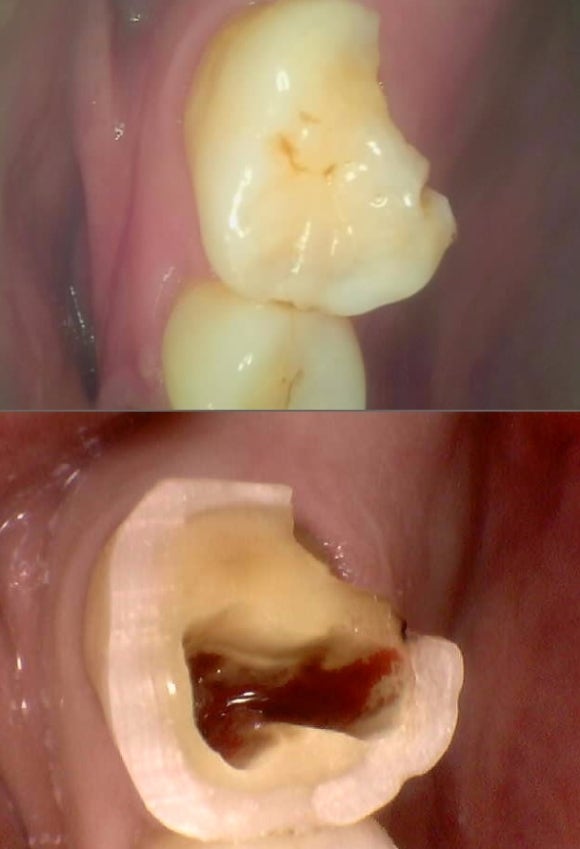

상기 환자 어금니 파절로 증상이 심해서 내원하심.

일단 머리가 심하게 부러져 있고 증상이 심하다는것은,

치아 뿌리에도 파절이 가 있다는 것을 전제로 치료를 시작을 함.

4번 정도 신경치료를 해도 신경관에서 피가 나오고 증상 개선은 없으시고

점점 더 심해지는 느낌이 든다고 하심.

더이상 신경문제가 아닌

뿌리 파절로 인한 증상임을 확정하고 (사진상엔 미세 파절은 절대 안보여서 증상으로 접근함)